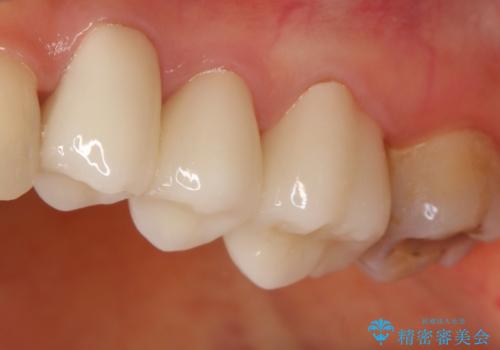

- 定期健診にて虫歯が見つかった患者さんです。県外からお越しいただいている事もあり、かなりお久しぶりの来院でした。歯と歯の間のところと銀歯の下が虫歯になっていました。被せ物はオールセラミッククラウンで治療しました。

銀歯を外すとかなり大きな虫歯になっていました。幸いぎりぎりのところで神経まで虫歯は広がっていなかったため、症状が出ない事を確認した後、オールセラミッククラウンで治療しました。虫歯除去後、残っている歯質が少なかったため、破折抵抗を考慮し部分的な被せ物ではなくクラウンを選択しました。

※被せ物では歯と被せ物の適合がとても大切になります。適合が悪い被せもの(歯と被せものの間に隙間がある)を入れるとそこに汚れが溜り虫歯の原因となります。当院では精度が高い被せものを追求するため、サージテル(拡大鏡)や型取りの材料にシリコン材を使用しています。